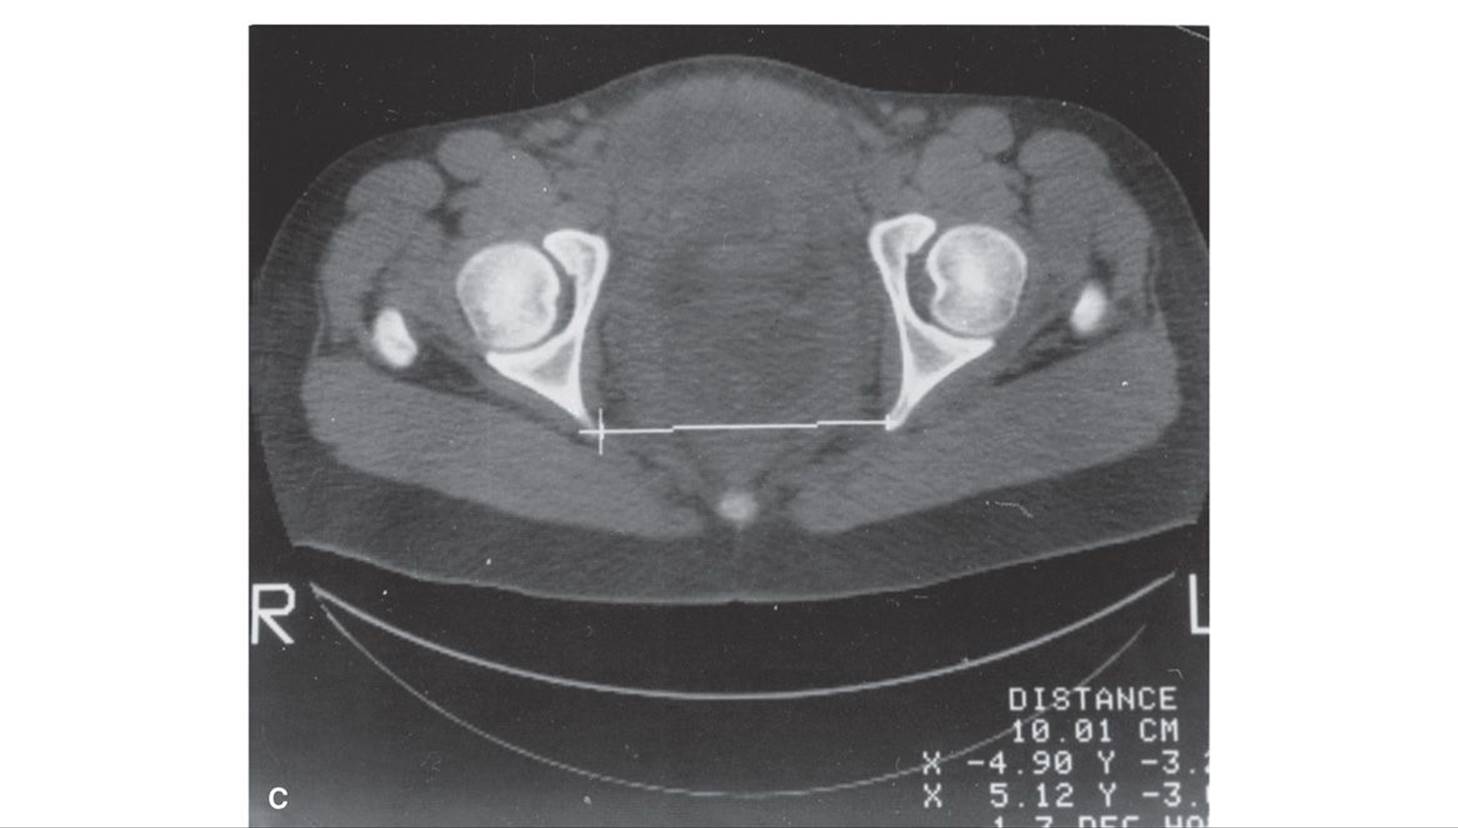

Advantages of pelvimetry with computed tomography (CT), such as that shown in Figure 23-4, compared with those of conventional x-ray pelvimetry include reduced radiation exposure, greater accuracy, and easier performance. With either method, costs are comparable, and x-ray exposure is small (Chap. 46, p. 934). Depending on the machine and technique employed, fetal doses with CT pelvimetry may range from 250 to 1500 mrad (Moore, 1989).

FIGURE 23-4 A. Anteroposterior view of a digital radiograph. Illustrated is the measurement of the transverse diameter of the pelvic inlet using an electronic cursor. The fetal body is clearly outlined. B.Lateral view of a digital radiograph. Illustrated are measurements of the anteroposterior diameters of the inlet using the electronic cursor. C. An axial computed tomographic section through the midpelvis. The level of the fovea of the femoral heads was ascertained from the anteroposterior digital radiograph because it corresponds to the level of the ischial spines. The interspinous diameter is measured using the electronic cursor. The total fetal radiation dose using these three exposures is approximately 250 mrad.